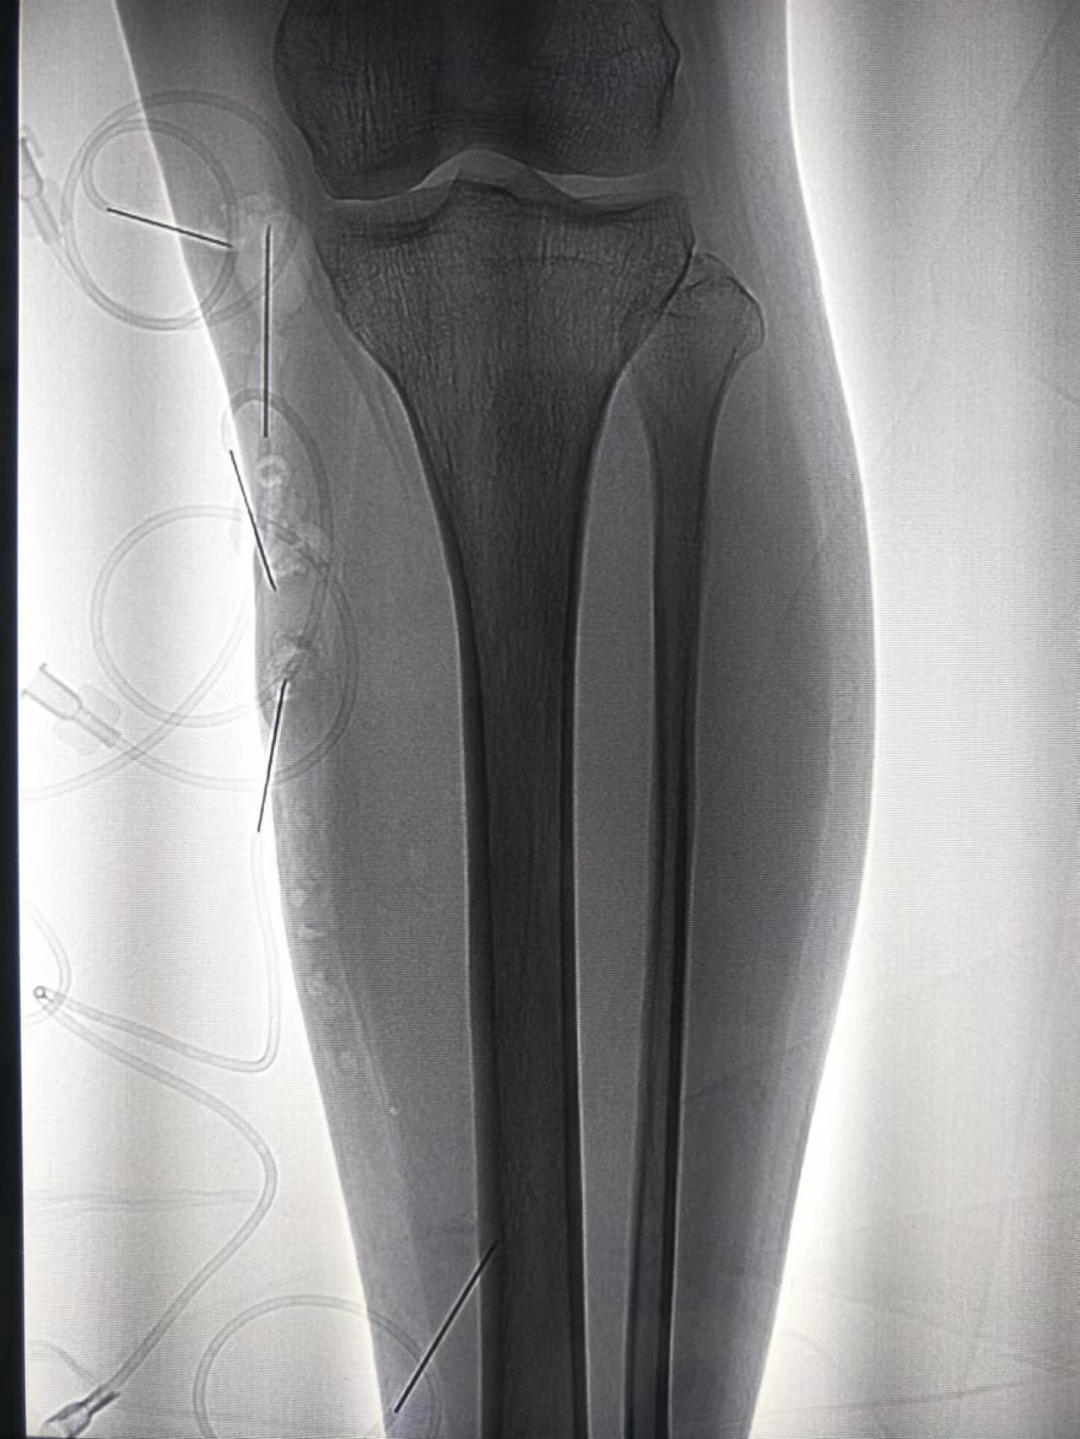

▲术中造影:大隐静脉明显曲张

▲术中注射硬化剂后